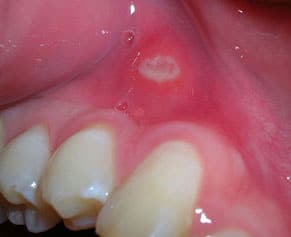

Ulcerative stomatitis

A bad health condition, immune suppression (chemotherapy or radiotherapy), or lacking of oral hygiene can lead to oral mucosa inflammation. Besides redness, swelling, burning and pain, canker sore, tears in the tissue, blisters or abscesses may occur. Also numbness, difficulties to swallow or even loss of taste can be symptoms of an oral mucosa inflammation. The change to an ulcerating inflammation goes along with profound, painful abscesses spreading from the alveolar ridge all over the oral mucosa, sometimes accompanied by strong pain, fever, involuntary flow of salvia out of the mouth, loss of gum and offensive breath.